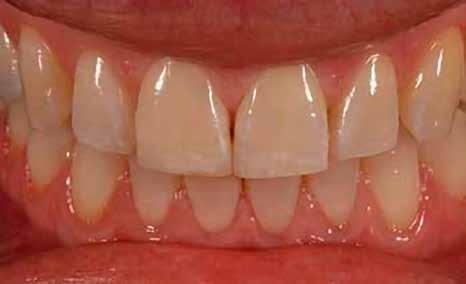

A fogászati kezelések során manapság már nem kizárólag az esztétikai megjelenés helyreállítására törekszünk. Sokszor a kedvezőtlen esztétikai megjelenés hátterében álló okok következményes módon a fogazat funkcionális működését is károsítják, így a kezelések során ezeknek a helyreállításával is foglalkoznunk kell. A különböző funkcionális és esztétikai diszkrepanciák kezelésére számtalan módszer létezik, ám ezen fogászati beavatkozások mindegyikében közös, hogy a kivitelezésük során nagyon szoros együttműködésre van szükség a kezelést végző fogorvos és a munkáját segítő fogtechnikus között. Az alábbi esetbemutatás során egy fiatal hölgypáciens fogazatának héjak alkalmazásával történő esztétikai és funkcionális rehabilitációját szeretnénk ismertetni.

Esetbemutatás

A 19 éves hölgypáciens azzal a kéréssel jelentkezett a rendelőnkbe, hogy szebb fogakat szeretne. Az első konzultáció alkalmával megkérdeztük, hogy mi zavarja leginkább a fogazatának jelenlegi megjelenésében, valamint azt is megbeszéltük vele, hogy milyen végeredmény elérése esetén lenne maradéktalanul elégedett. Ebben az esetben a kezelési célokat az alábbiakban határoztuk meg:

A páciens fogazata esztétikai megjelenésének és funkcionális működésének a lehető legtöbb, saját foganyag megtartása mellett történő helyreállítása (1. és 3. ábra). A lehető legideálisabb esztétikai végeredmény elérése érdekében néhány esetben a fogak alakjának módosítá -

sára is szükség van (2. és 4. ábra).

A kezelés megtervezése során kifejezett jelentősége van annak, hogy jó kommunikáció legyen a páciens, a fogorvos és a fogtechnikus között. A páciens leendő fogazatának természetes megjelenését a kezelésben részt vevő team szakmai felkészültsége, gyakorlati tapasztalata és a kezelés sikerességének irányába történő elkötelezettsége biztosítja. A beavatkozások megkezdése előtt megtörtént a páciens anamnézisének a felvétele, valamint a klinikai kivizsgálását is elvégeztük. Ezt követően lenyomatokat készítettünk a kiindulási állapotról, majd a kiindulási helyzetet extra- és intraorális fotók segítségével is rögzítettük (13. a-c. ábra).